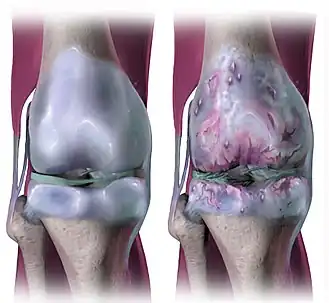

Artrose[1] is in de geneeskunde de naam van een aangeboren of verworven degeneratieve aandoening aan het kraakbeen in gewrichten.

Artrose wordt in de volksmond ook wel gewrichtsslijtage genoemd. Artrose ontstaat doordat er meer gewrichtskraakbeen verloren gaat dan er door het lichaam geproduceerd kan worden.[3] Het kraakbeen verslechtert en soms verdwijnt het helemaal. Bij artrose vermindert ook de vloeistof in het gewricht. Deze vloeistof, synoviale vloeistof of synovium geheten, is nodig om het gewricht soepel te laten draaien en om schokken te absorberen.[4] Door slijtage van gewrichtskraakbeen en een vermindering van de schokabsorberende vloeistof in de gewrichten kunnen botten over elkaar schuren, wat veel pijn veroorzaakt. Artrose komt voornamelijk voor in de gewrichten van de handen, knieën, schouders, nek en heupen. Iedereen boven de zestig jaar lijdt eigenlijk wel aan een röntgenologisch waarneembare mate van artrose; soms begint het al op aanzienlijk jongere leeftijd.

Artrose wordt gekenmerkt door pijn tijdens beweging van het aangedane gewricht en door een stijf of stram gevoel. Het gewricht is vooral stijf na een tijdje niet bewegen, zoals 's ochtends. Verder kunnen ernstig aangedane gewrichten een krakend gevoel geven en kan er bewegingsbeperking ontstaan en soms zelfs een standsverandering. Soms kan vochtophoping optreden in het gewricht, als uiting van een ontstekingsreactie. Bij artrose van de handen ontstaan vaak verdikkingen in de PIP- en DIP-gewrichten, dit zijn de noduli van Bouchard en Heberden. De basisgewrichten van de duim zijn in de hand vaak het ergst aangetast. Door de pijn wordt de duim minder gebruikt. Hierdoor kunnen de spieren van de duim dunner worden en kracht verliezen.

Artrose wordt gediagnosticeerd aan de hand van het klinische beeld. Soms wordt een röntgenfoto gemaakt om de diagnose te bevestigen. Op de röntgenfoto is de verminderde kraakbeendikte indirect af te leiden uit het te dicht opeen liggen van de botuiteinden; het kraakbeen zelf is op een röntgenfoto niet te zien. Daarnaast kunnen door artrose osteofyten ontstaan, botuitsteeksels en -haken aan de randen van de gewrichtsvlakken. Deze zijn op een röntgenfoto wel te zien. Er zal doorgaans een foto onder belasting worden gemaakt, dus bij artrose aan de knieën en bij artrose van de heup, zal een foto worden gemaakt van een staande patiënt.

Artrose kan eigenlijk worden gezien als een normaal proces van de gewrichten zodra er sprake is van onderbelasting van een gewricht oftewel een tekort aan belasten van het totale kraakbeenoppervlak.[10] Dit heeft tot gevolg dat de gewrichten minder kraakbeen hebben en dat er pijn bij beweging gaat ontstaan. Vaak wordt over artrose gesproken als 'slijtage' van de gewrichten, maar van puur mechanische slijtage zoals men bij machineonderdelen ziet, is geen sprake; zowel bot als kraakbeen zijn levende weefsels met cellen die actief betrokken blijven bij het functioneren van het weefsel.